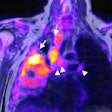

PET/CT's role develops in breast cancer follow-up